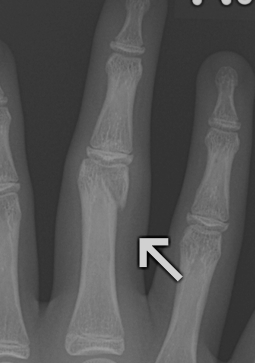

Condylar fractures of head of P1 / P2

Mechanism

- torsional and valgus impaction

London classification

Type 1 Unicondylar, undisplaced

Type 2 Unicondylar, displaced

Type 3 Bicondylar

Displaced unicondylar

- percutaneous K wire

- ORIF with screw